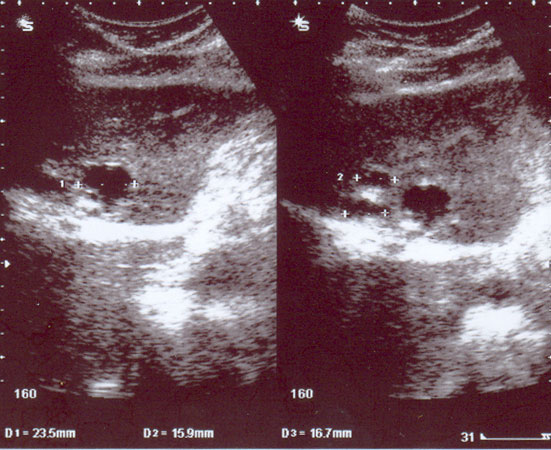

9. The result of the CT scan of the thorax and liver done on 21 February 2008 indicated:

• There is a small new left-sided pleural effusion.

• There is extensive volume loss demonstrated within the left hemithorax. This is secondary to left upper lobe collapse.

• There is mildly heterogenous pattern of enhancement to the collapse lung at the perihilar region.

• There is a possible recurrence of a left hilar pulmonary mass causing bronchial obstruction.

• There is a 8 mm pulmonary nodule in the right upper lobe.

• There is an enhancing mass adjacent to the falciform ligament.

• There is a 12 mm hepatic density within segment 6 of the liver.

• There are several subcentimetre hypodensities scattered throughout the liver which are too small to characterize.

• There is a left adrenal mass measuring 3.7 cm.

• There is a right adrenal mass measuring 2.7 cm.

• There is no destructive bony lesion identified.